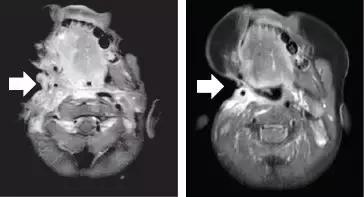

其中有一些晚期患者的病灶完全消失了:

我们可以清楚的看到,这位极晚期的肉瘤患者,肿瘤已经快要填满双肺,经过LOXO-101治疗12周期,肿瘤几乎完全消失!

治疗前 治疗3周期第1天 治疗13周期第1天